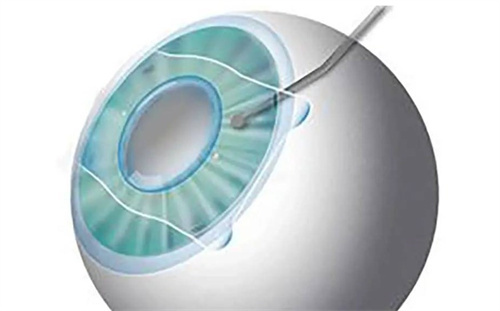

ICL晶体植入术是一种通过将特制的软性晶体放置于眼内后房,自然调整光线聚焦位置,从而达到矫正视力的目的。这种晶体由胶原蛋白聚合物制成,具有良好的透氧性和稳定性,能够长期可靠地留在眼内。